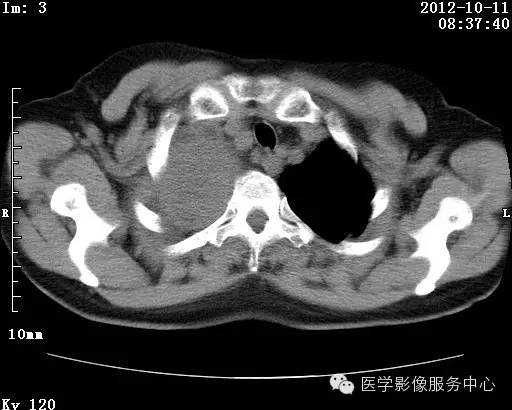

病史:女 65岁咳嗽咳痰 右肺巨大肿块就诊。

错构瘤的发病年龄多数在40岁以上,男性多于女性。 绝大多数错构瘤(约80%以上)生长在肺的周边部,紧贴于肺的脏层胸膜之下,有时突出于肺表面。其特征钙化为爆米花样钙化,内有脂肪软骨成分等等。最常见的部位是胸膜下肺实质内,其次为主支气管或肺叶、肺段支气管内。

理论上肺错构瘤为良性肿瘤,其结节形态、边界、与胸膜关系、与肺门关系、淋巴结肿大及与血管关系均应符合良性肿瘤的特点。

由于不典型错构瘤极易误诊为周围型肺癌和/或结核球,故应与二者鉴别。

结核球患者既往病史中可能有明确的肺结核病史,周围多可见卫 星病灶,增强扫描无强化或仅有包膜强化,此外纵隔 肺门淋巴结多有钙化征象;

周围型肺癌绝大多数边界不光整, 可见短毛刺,钙化不常见,爆米花样钙化更罕见,而 且往往合并有纵隔肺门淋巴结增大增多,患者临床症状较为明显。